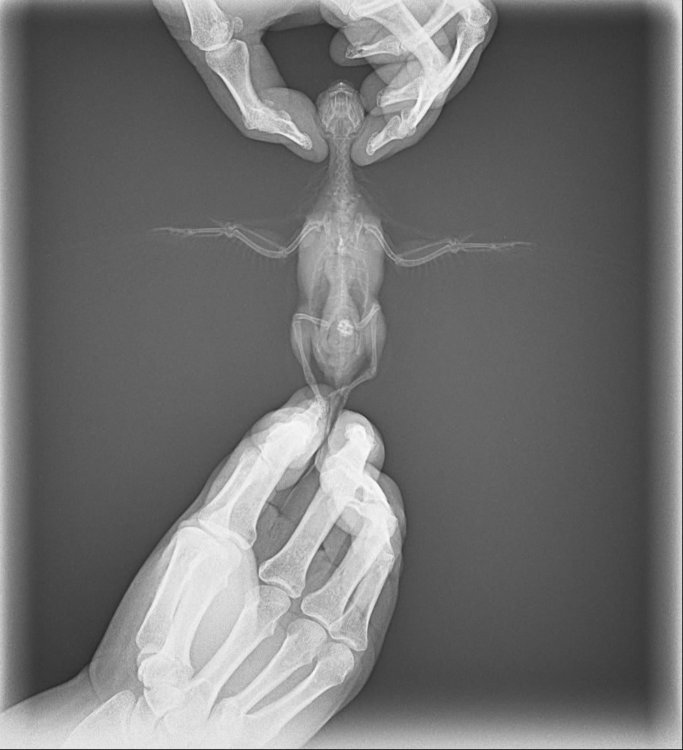

олег 19 Опубликовано 5 июня, 2019 Автор #3 Опубликовано 5 июня, 2019 @Delfin мы покупали ее как самца ,около 2х месяцев ей было ,нос сразу стал менятся в бежевый а затем в коричненвый цвет,голубым и синим как у самцов он не был,поэтому подумали что это девочка. список чем мы лечились:байтрил,лобелон,гепатовет,лиарсин,смекта,сумамед,ципровет,элвестин,нистатин,бифидум пили,фуросемид,эуфилин ,чиктоник пили,обрабатавались от клеща как думали 2 раза название не помню .Щас делаем ингаляции с корвалолом и эуфилином ,так же пьем лиарсин смекту она отрыгивает пищу ,стала плохо есть посоветовали попить нистатин для зоба может,больше пока ничего не пьем. вот снимок мы его делали в феврале 24 числа

Delfin Опубликовано 5 июня, 2019 #4 Опубликовано 5 июня, 2019 ....тогда похоже у вас самка. Но и у самок куча проблем часто по женски. Нос коричневый говорит о большом кол-ве гармонов и ето плохо,ибо проблема с яичниками.. снимки у нас только Зося читает,стукнитесь к ней http://www.mybirds.ru/forums/index.php?&showuser=4292

Zosia Опубликовано 11 июня, 2019 #10 Опубликовано 11 июня, 2019 Хороший вес. Пристойный рентген. Желубок там мускульный, с конкрементами (песок убрать навсегда). Липомка на пузе, не видится критичной (нужен снимок в латеральной проекции). Помет на микроскопию сдавайте (копрограмма),пусть смотрят жиры,жирные кислоты,мыла, кристаллы, йодофильную флору, простейших,глистов- короче все что могут. Какие сейчас ЖАЛОБЫ по состоянию птицы.